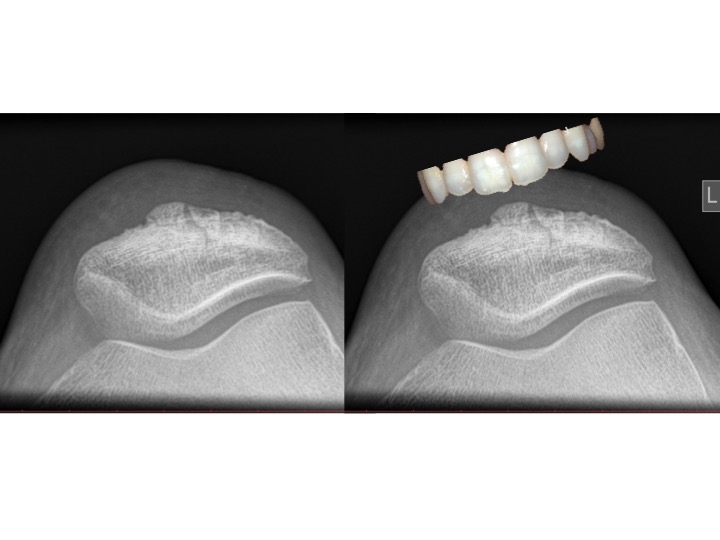

40 years old man with knee pain.

Long history of bodybuilding

What is the sign?

Patellar tooth sign of degenerative enthesopathy

Vertical ridging of the osteophytes at the anterior surface of the patella can resemble dentate structure (tooth sign)

It is consistent with an enthesopathy related to stress at the attachement of quadriceps.

vertical ridging of the patellar insertion of the quadriceps tendon which can resemble a dentate structure, i.e. "tooth" sign.

frequent finding with degenerative disease

degenerative enthesophyte formation on superior aspect of patella (site of insertion of the quadriceps tendon) as seen on axial or skyline (sunrise) view

seen as saw-tooth projections:

best seen on axial or skyline view of patella on its superior and anterior surface